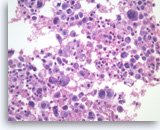

Plasma cell neoplasm,

Pancreas FNA, Cell Block.

Single tumor cells show eccentric nuclei and occasional binucleation. Flow cytometry demonstrate CD38 positive B-cells without surface immunoglobulin expression. The cytomorphologic features along with flow cytometry results are consistent with plasma cell neoplasm. CD138 immunostain can be performed on the cell block section to support the diagnosis if needed.

40X

Plasma cell neoplasm,

Pancreas FNA, Cell Block.

Single tumor cells show eccentric nuclei and occasional binucleation. Flow cytometry demonstrate CD38 positive B-cells without surface immunoglobulin expression. The cytomorphologic features along with flow cytometry results are consistent with plasma cell neoplasm. CD138 immunostain can be performed on the cell block section to support the diagnosis if needed.

40X